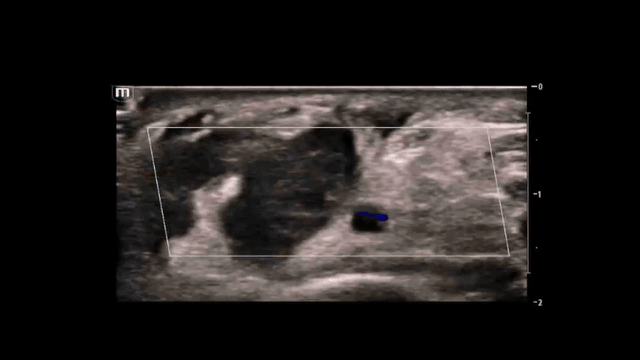

This was our initial view of the right wrist on ultrasound.

• The radial artery (circled) is visualized at a depth of ~1.3 cm just to the right of the midline of the image.

• Sliding the probe superiorly and inferiorly revealed a well circumscribed, complex, hypoechoic structure present just lateral (to the left) of the radial artery.